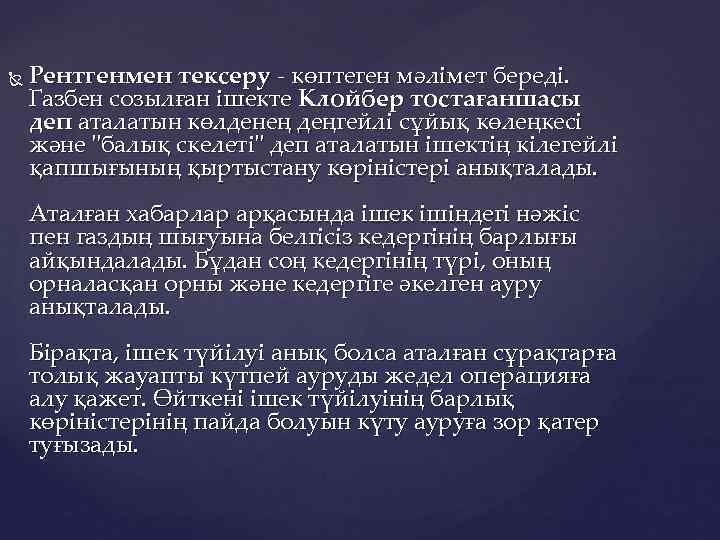

Рентгенмен тексеру - көптеген мәлімет береді. Газбен созылған ішекте Клойбер тостағаншасы деп аталатын көлденең деңгейлі сұйық көлеңкесі және "балық скелеті" деп аталатын ішектің кілегейлі қапшығының қыртыстану көріністері анықталады. Аталған хабарлар арқасында ішек ішіндегі нәжіс пен газдың шығуына белгісіз кедергінің барлығы айқындалады. Бұдан соң кедергінің түрі, оның орналасқан орны және кедергіге әкелген ауру анықталады. Бірақта, ішек түйілуі анық болса аталған сұрақтарға толық жауапты күтпей ауруды жедел операцияға алу қажет. Өйткені ішек түйілуінің барлық көріністерінің пайда болуын күту ауруға зор қатер туғызады.

а) Он екі елі ішек стенозы. Ішектің түйілуі түрлерінің рентгендік көрініс ерекшеліктері б) Ащы ішектің жоғарғы бөлігінің түйілуі. в) Ащы ішектің төменгі бөлігінің түйілуі. г) Тоқ ішектің түйілуі. 1 - Қарынның ауамен толуы. 2 - Ащы ішектің желмен толуы (Клойбер симптомы). 3 – Сұйық. 4 - "Аркада ". 5 - Керкринг қатпарлары. 6 - Ауамен созылған соқыр ішек. 7 – Гаустрлар. 8 - Ішекті бітеген ісік. 9 - Ауамен созылған тоқ ішек. 10 - Тарылудан темен, ішінде